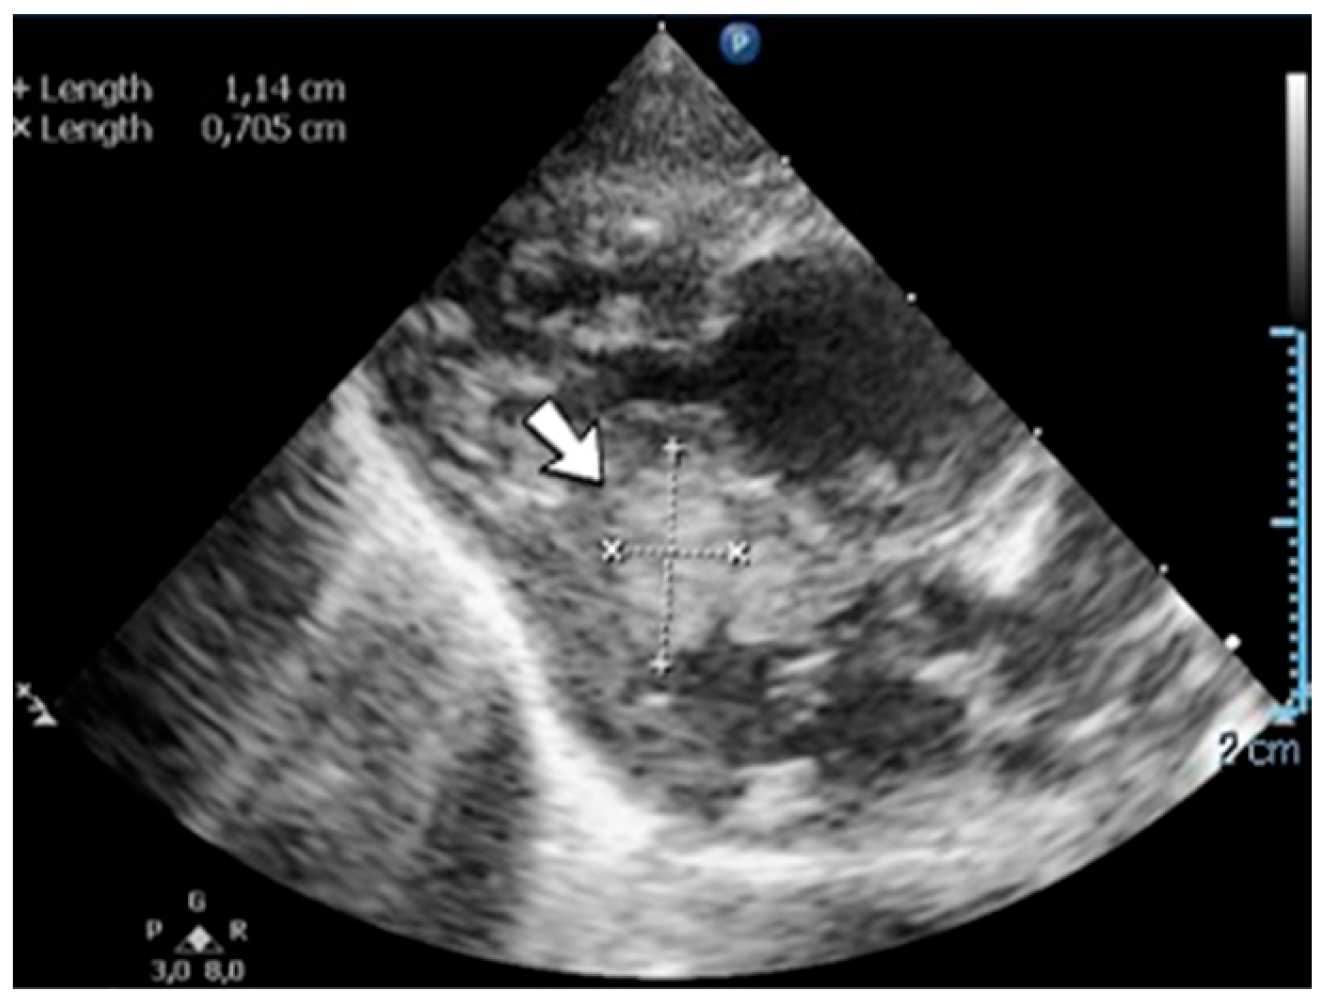

4.37. Case No. 37—Postnatal Intracardiac Thrombosis

A 1-day-old male neonate (unknown gestational age, 3.00 kg) presented with a complex congenital cardiac malformation for an elective surgical procedure. Admission laboratory findings showed elevated c-reactive protein, procalcitonin, and slightly modified coagulation tests. A routine cardiovascular ultrasound showed multiple thrombi in the left ventricle (Figure 17). Continuous heparin infusion was initiated. The patient’s condition continued to deteriorate, developing pneumothorax at one month of life, leading to a negative outcome.

Figure 17.

Intracardiac thrombosis was identified on cardiac ultrasound in the left ventricle.

Genetic testing confirmed inherited thrombophilia, with positive Prothrombin G20210A and MTHFR A1298C heterozygous gene mutations and Antithrombin, Protein S, and Protein C deficiencies. A moderate elevation of PAI-1 levels was also detected. There was a positive maternal history of miscarriage.